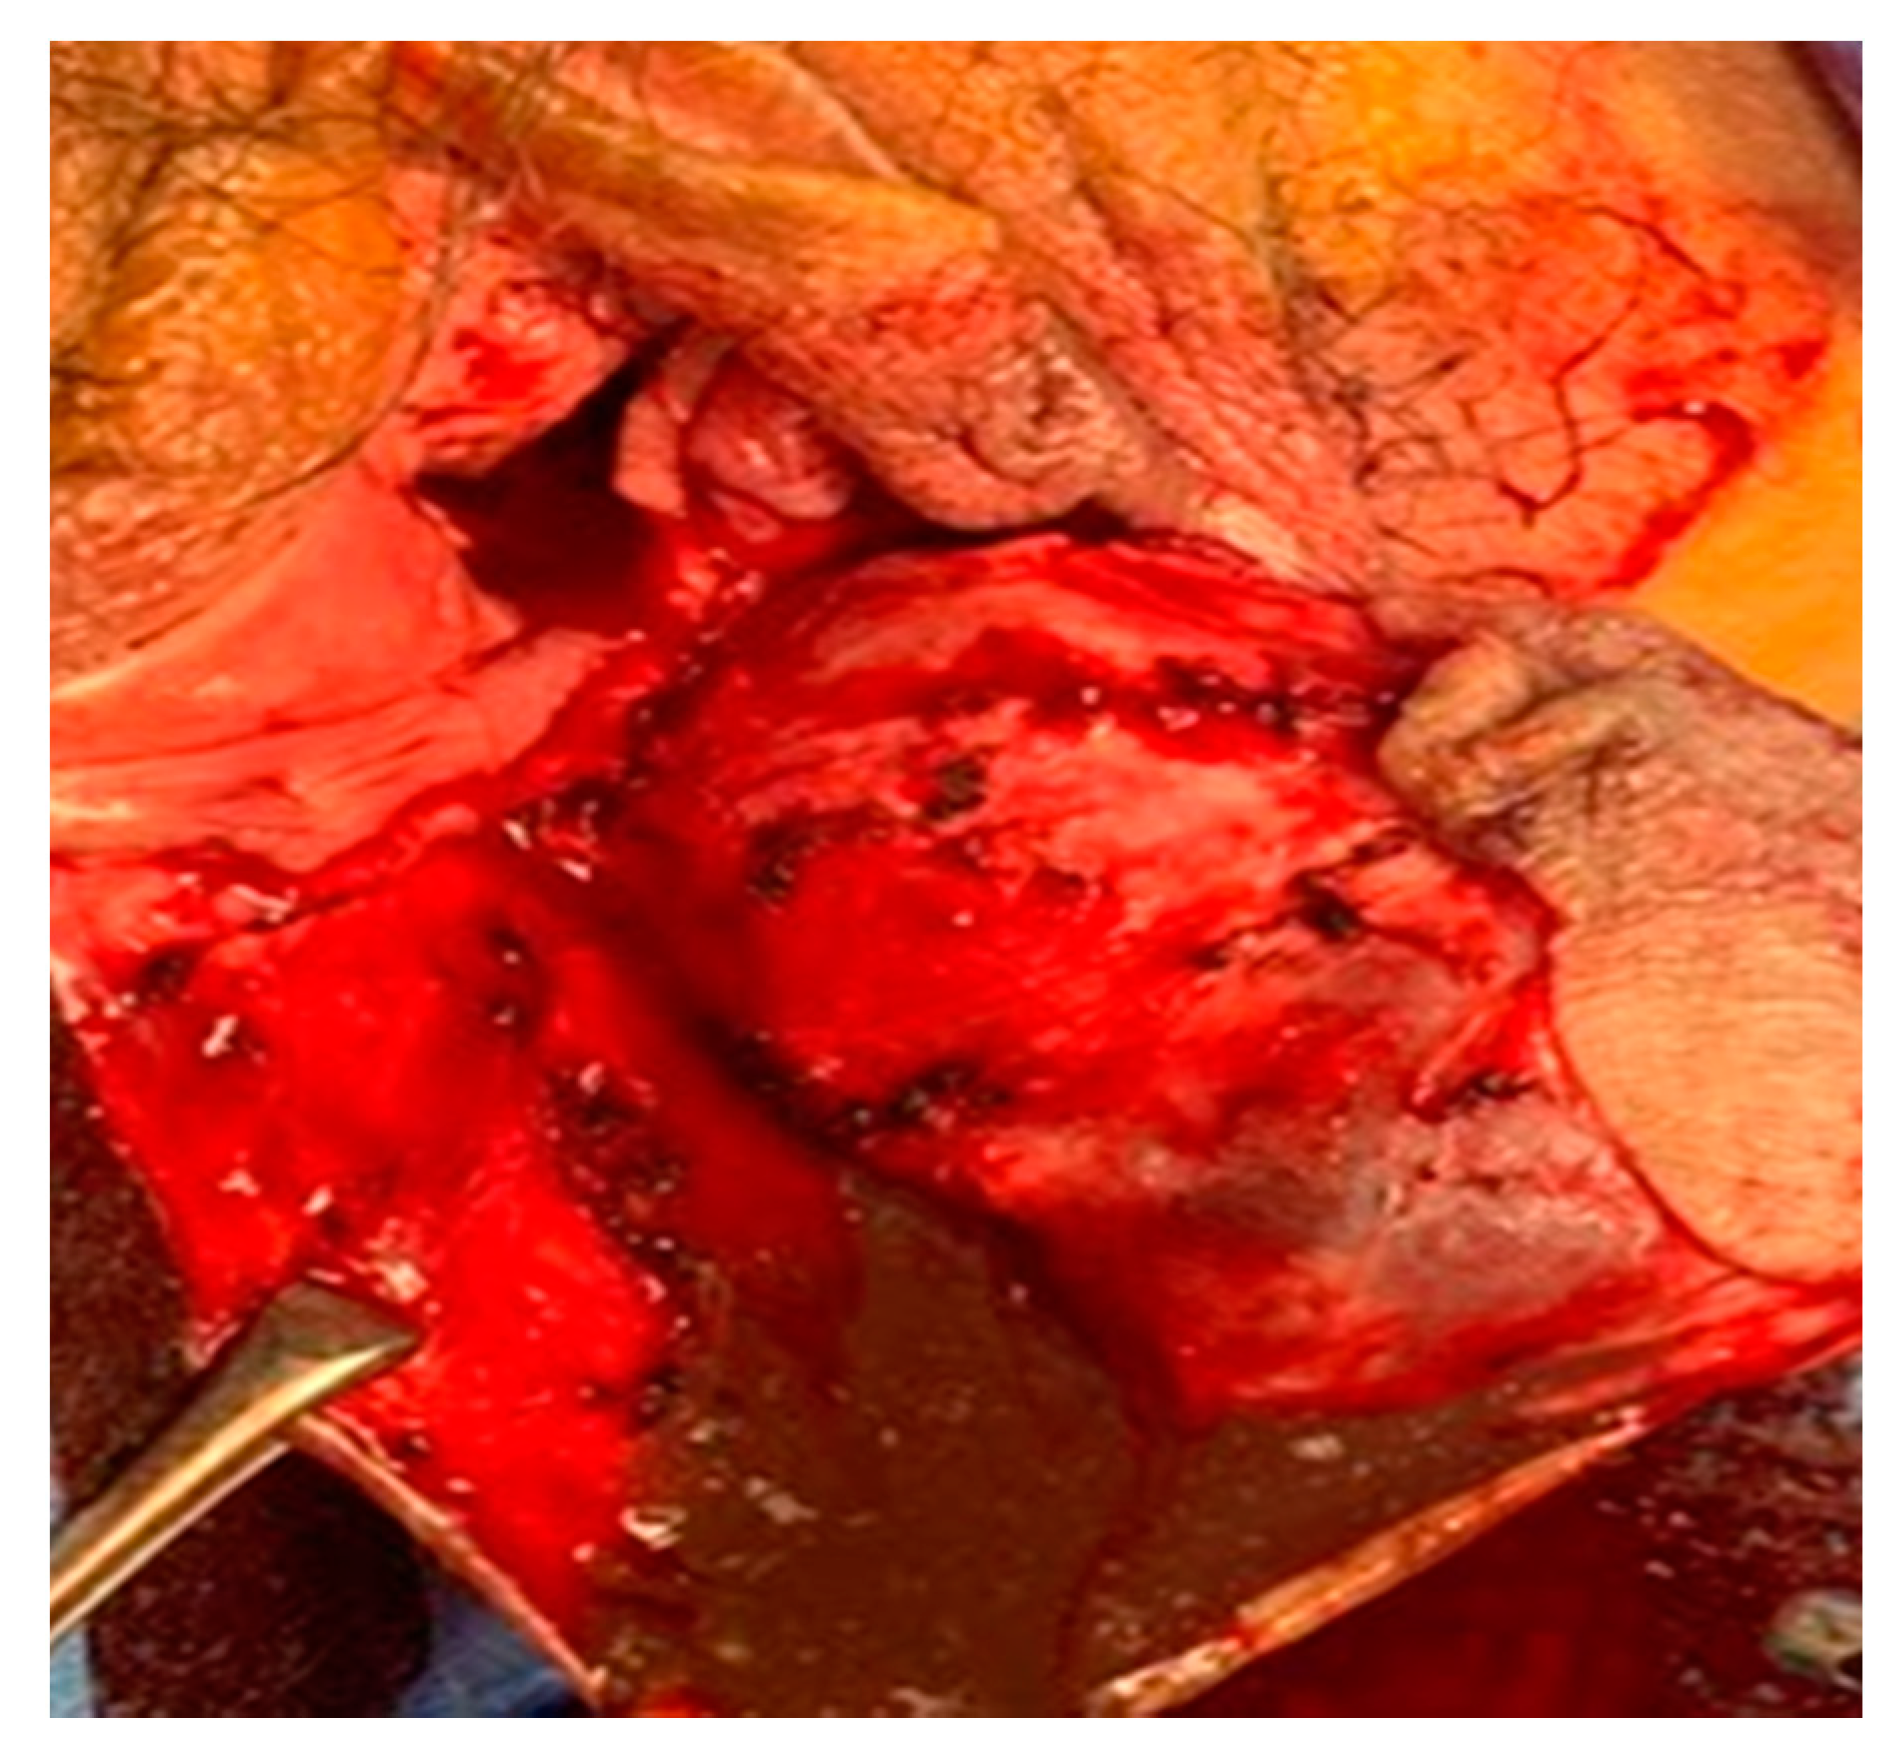

A Huge Hemorrhagic Epidermoid Cyst of the Perineum with Hypoechoic Semisolid Ultrasonographic Feature Mimicking Scar Endometriosis

Nam, G.; Lee, S.R.; Eum, H.R.; Kim, S.H.; Chae, H.D.; Kim, G.J. A Huge Hemorrhagic Epidermoid Cyst of the Perineum with Hypoechoic Semisolid Ultrasonographic Feature Mimicking Scar Endometriosis. Medicina 2021, 57, 276. https://doi.org/10.3390/medicina57030276